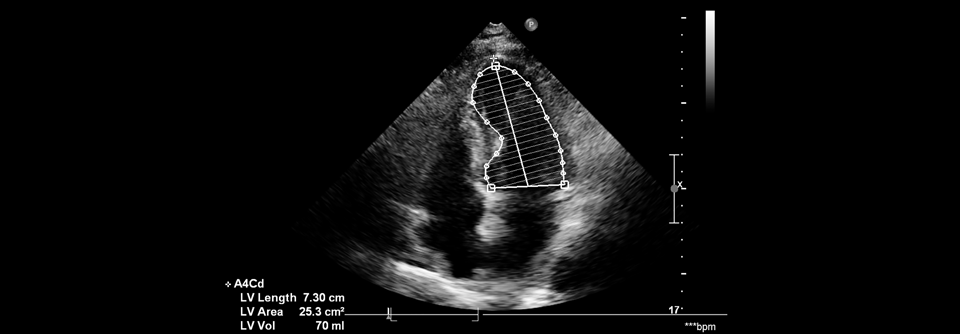

Adipös, schlecht eingestellter Diabetes, Herz- und Niereninsuffizienz – was lässt sich therapeutisch rausholen?

Ein strafferes Blutzuckermanagement reicht bei der Vielzahl an Begleiterkrankungen nicht aus.